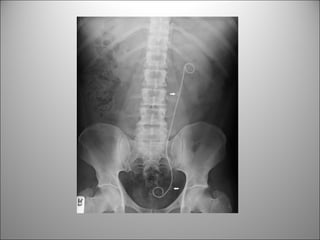

• EVALUE GLOBALMENTE: clips, DIU, Bario,

artefactos externos

CALCIFICACIONES Y ARTEFACTOS

PATOLOGÍA FRECUENTE

LITIASIS

MIOMAS

LITIASIS BILIAR

CALCIFICACIONES AORTICAS